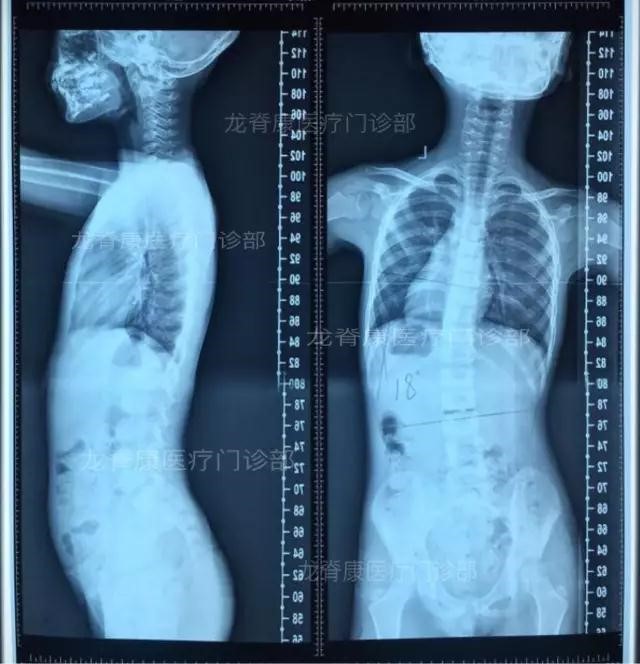

杜主任给孩子做了非常仔细的检查,并用脊柱侧弯水平角度仪给孩子进行背部倾斜角的测量。

并让孩子拍了X光片: